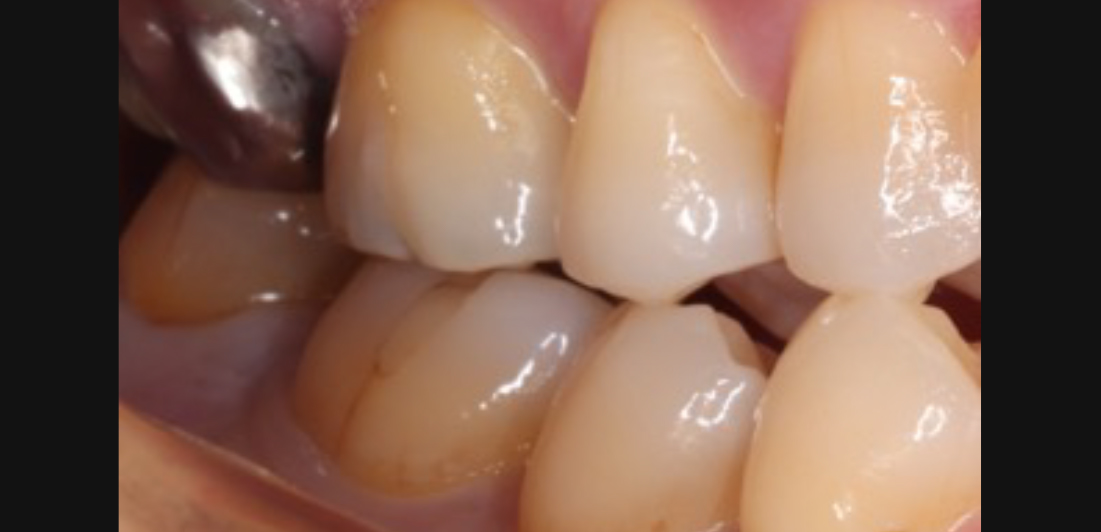

移植した状態です。炎症もなく問題なく経過しているのがわかります。

被せ物が入った状態です。何ら問題なく機能しております。

口腔内写真です。特に炎症もなく 経過しております。